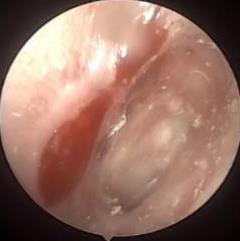

• 耳内镜下耳屏软骨-软骨膜鼓膜修补术后的短期疗效观察

摘要:目的 探讨耳内镜下耳屏软骨-软骨膜鼓膜修补术后的短期疗效。方法 回顾性分析2019年9月-2022年8月该院收治的78例鼓膜穿孔患者的临床资料,患者均采用耳内镜下鼓膜修补术。术后随访3个月,观察鼓膜形态和穿孔愈合情况,记录内镜图像、干耳时间、术前术后听力及耳鸣情况,以及外耳道狭窄等并发症的发生率。结果 术后3个月,鼓膜穿孔愈合率为97.44%(76/78),愈合良好,平均气导听阈较术前明显改善,气骨导间距较术前明显缩小,耳鸣较术前明显改善,差异均有统计学意义(P<0.05)。干耳时间为(4.21±1.12)周。术后出现肉芽5例,再穿孔2例,真菌感染2例,术腔感染、耳屏感染、外耳道狭窄和切口瘢痕各1例,所有患者术后均未发生面神经麻痹和感音神经性聋等严重并发症。结论 耳内镜下耳屏软骨-软骨膜鼓膜修补术是一种安全、有效的手术方法。根据术后愈合规律、内镜下鼓膜和外耳道形态特征,可为鼓膜修补术后正常中耳转归和并发症的诊疗,提供临床参考。